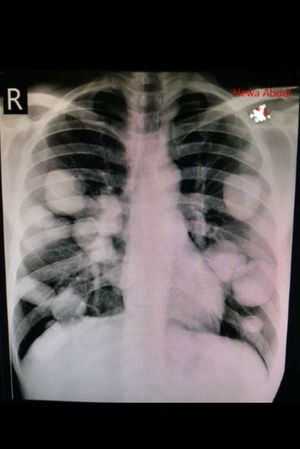

Guess Diagnosis ?!

I will take a stab at this, Tuberculosis

CF? Fibrous growth

Canon ball secondaries- choriocarcinoma